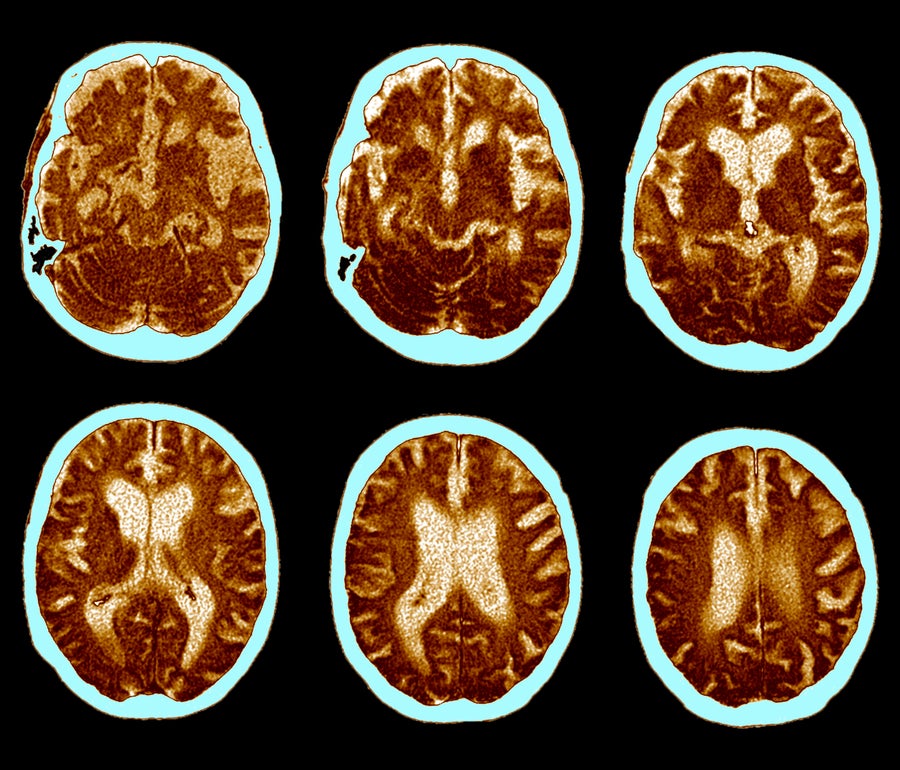

Brain CT scans of Alzheimer’s disease. ZEPHYR/Science Source